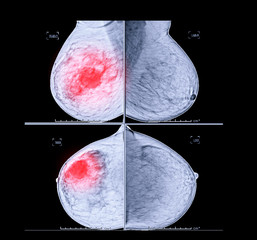

본원에서 유방 촬영, 유방 초음파를 시행한 50대 여성의 사례 |

비대칭 증가음영으로 사진상 미세석회화도 동반되어 있었습니다.

초음파상 이 부위에 종괴가 있었고, 총생검상 상피내암으로 진단 받고, 수술 후 0기암으로 최종 진단을 받았습니다.